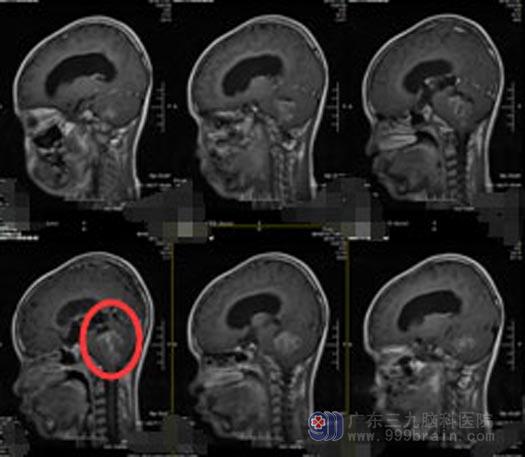

当地医院头颅CT检查提示:四脑室占位、梗阻性脑积水;广东三九脑科医院头颅MR检查结果:小脑蚓部-四脑室占位性病变,大小约36mm×33mm×35mm,四脑室扩大,脑干受压变扁,幕上脑室系统扩张,双侧侧脑室周围示间质性水肿。

诊断明确后,为减少术中出血,先给琪琪行右侧脑室穿刺外引流手术,再转放疗科行术前放疗,然后由综合神经外科鲁明副院长主刀在全麻下行“四脑室占位性病变切除术”,显微镜下见肿瘤呈棕黄色,质脆、硬混杂,边界相对尚清,与周围粘连紧密,小脑被压向两侧,侧方长入桥脑侧沟,向下挤压并侵犯脑干,瘤内有卒中,血供中等,分块全切肿瘤,手术经过顺利。

手术前

手术后